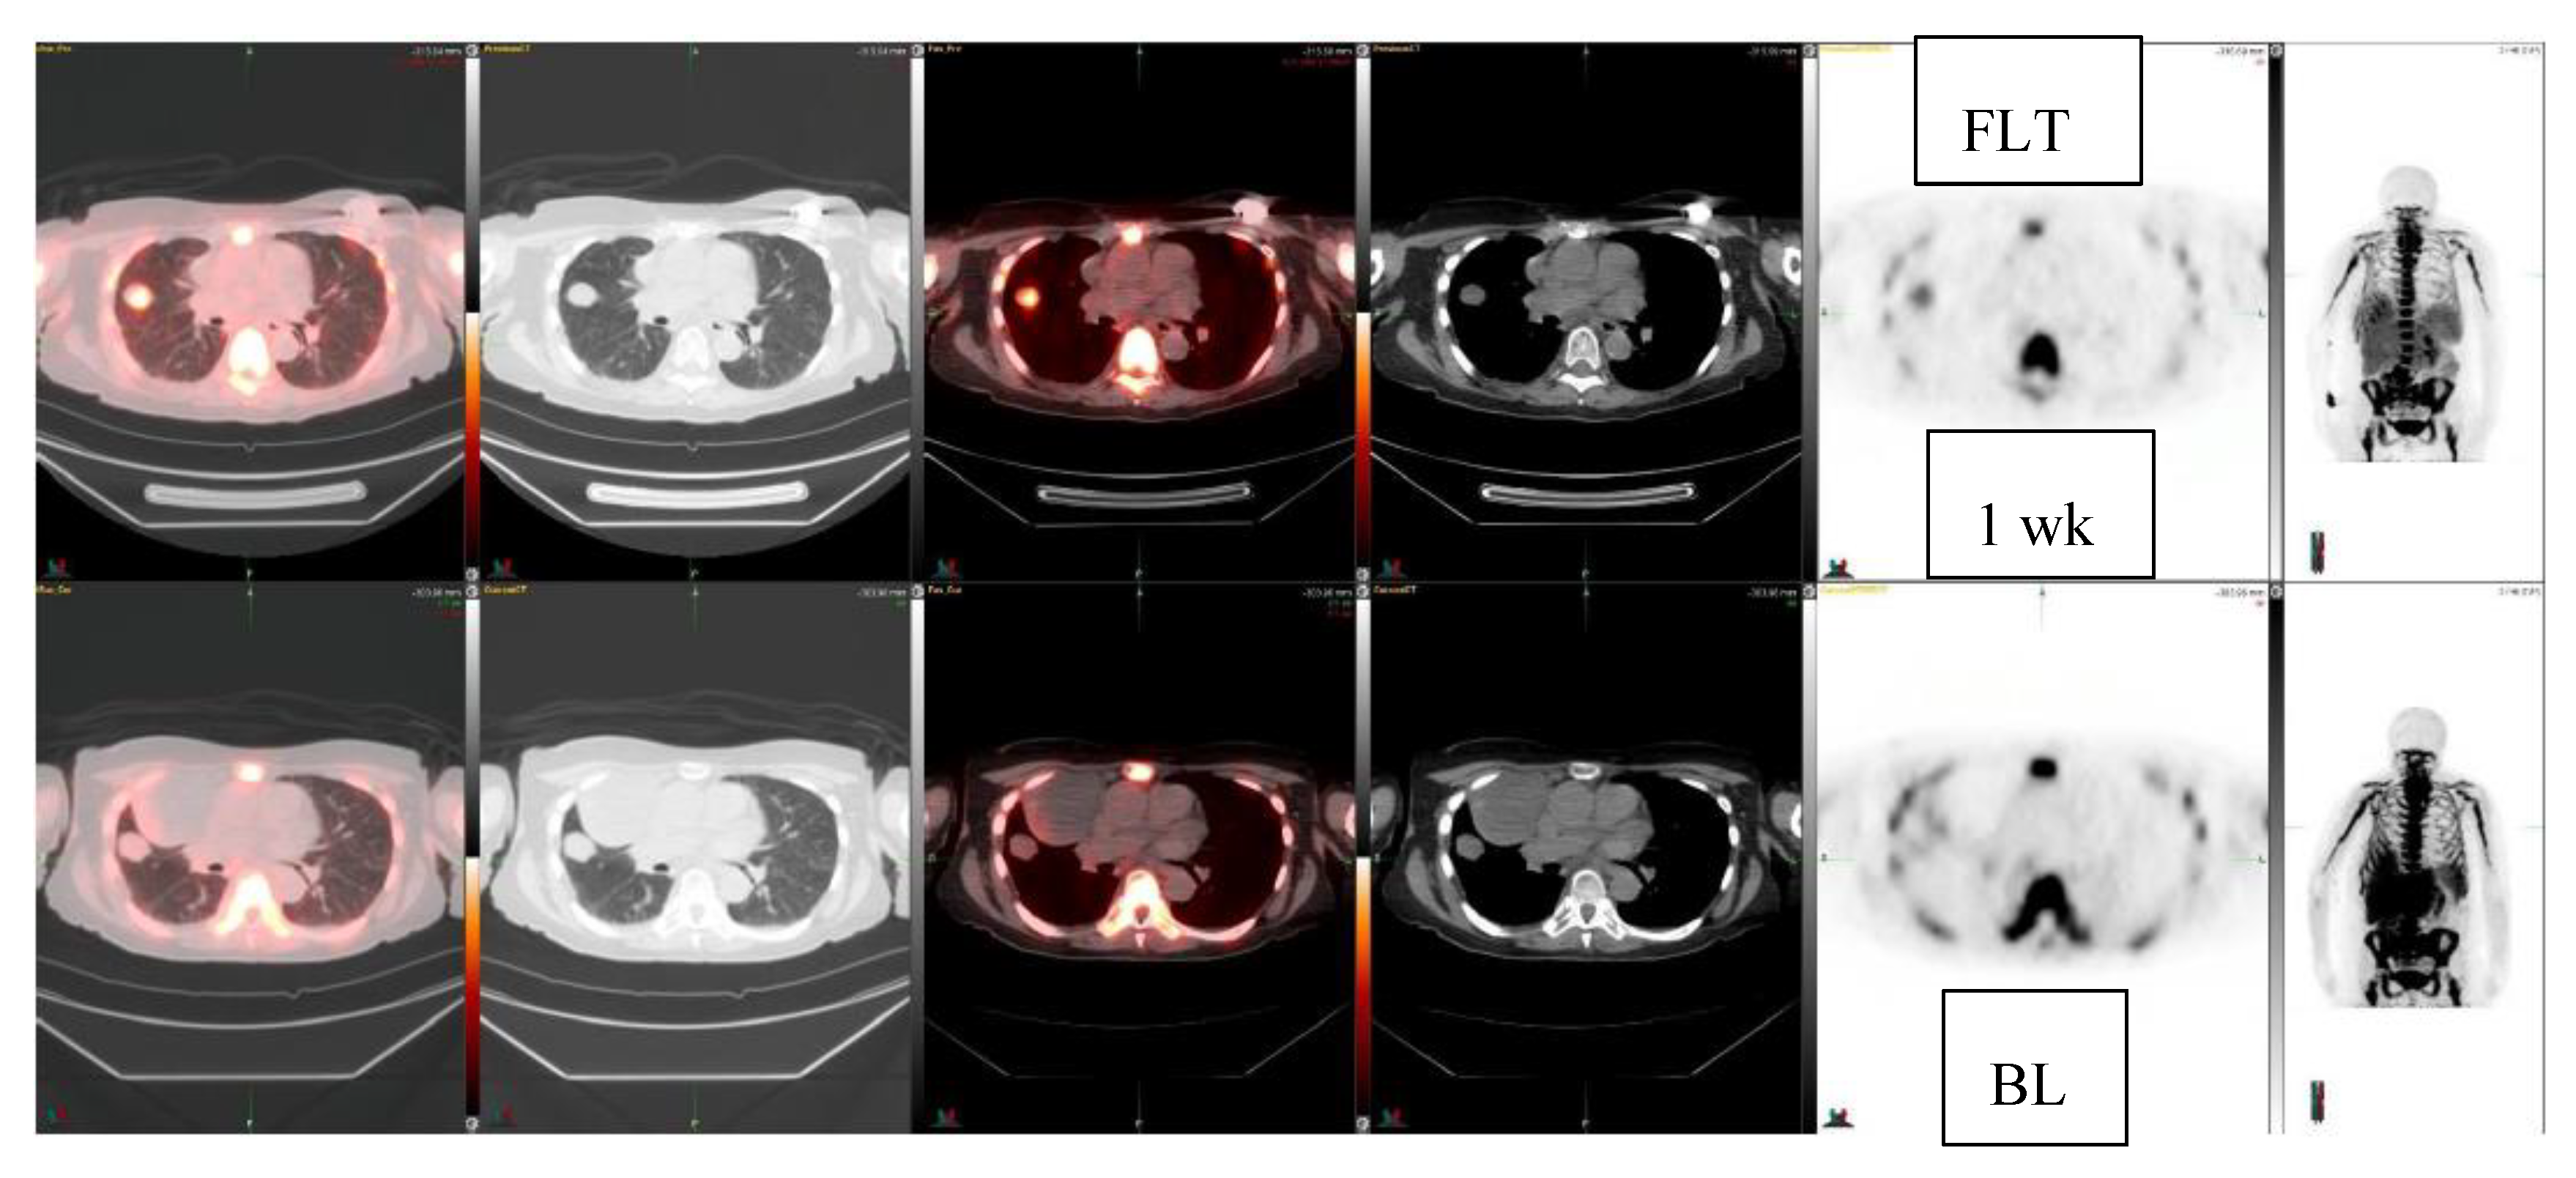

| 74/F | Fibrous tumor, pleura Lung mass | 3.0 2.4 × 1.9 | 1.7 2.5 × 2.0 1 week | Fibrous tumor 3.0→1.7 No FDG response | −43% |

| 61/M | Cardiac angiosarcoma, atrium, pericardium | 3.3 2.6 × 1.8 | 3.0 2.0 × 1.7 4 weeks | Another pericardium change 3.9→5.9 | +51% -9% |